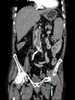

Aortic thrombosis

An aortic aneurysm is an enlargement (dilatation) of the aorta to greater than 1.5 times normal size. They usually cause no symptoms except when ruptured. [Source: Wikipedia ]